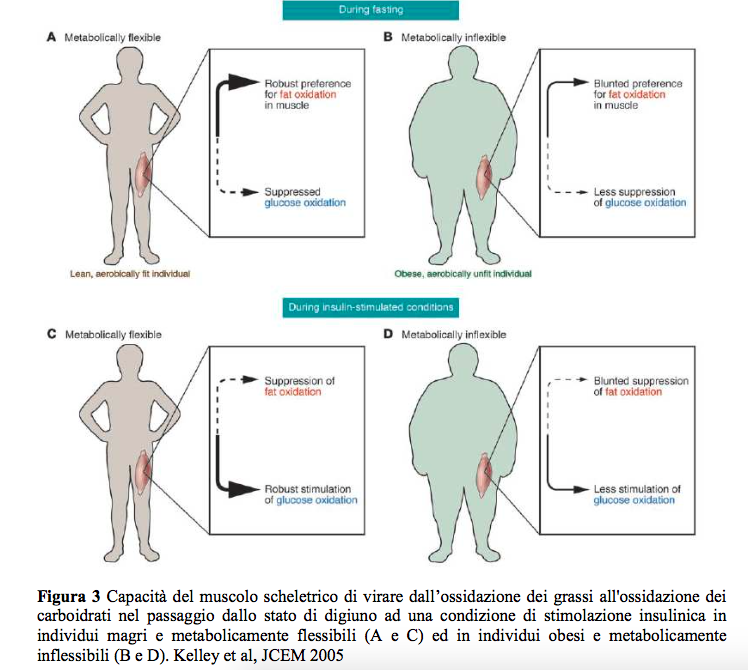

Purtroppo, tuttavia, non funziona così. Sarebbe troppo facile. Il muscolo che consuma i lipidi a riposo è una condizione metabolica fisiologica ma che purtroppo sempre meno persone hanno. Sindrome metabolica, insulino resistenza, elevati livelli di resistina, ecc portano la nostra condizione da ideale ad una merda (scusate la parolaccia ma era per rendere l’idea).

Il muscolo da brucia grassi si ritrova a consumare un mix di lipidi e carboidrati. Questo abbassa il dispendio calorico globale dell’organismo, la nostra macchina si ingolfa e al posto d’avere un motore che gira 3000 volte al minuto passa a 1000.

Per tornare ad essere dei buoni ossidatori ed accelerare il metabolismo, dobbiamo adottare tutte quelle strategie che insegnano al nostro organismo ad utilizzare in modo preferenziale un solo macronutriente: o grassi o zuccheri. Per assurdo (ma in fisiologia neanche tanto) le due strade opposte portano al medesimo risultato.

Dall’altra anche allenamenti molto molto blandi se fatti quando le nostre riserve di glicogeno epatico sono quasi esaurite, aiutano il muscolo ad aumentare la sua capacità d’ossidare meglio i grassi. Prende così un senso la corsa o la camminata in salita a digiuno mentre seguiamo una dieta low carb o chetogenica. L’obiettivo è aumentare l’ossidazione lipidica per un periodo di tempo rilevante (almeno 30′).

Ripetiamo perchè è importante, l’attività a basso impatto prende sempre di più un senso quanto più le riserve di glicogeno epatico sono basse, questo perchè l’organismo inizia a preservare il glucosio ed aumenta il metabolismo lipidico. In soggetti con una inflessibilità metabolico (col metabolismo bloccato), l’attività fisica moderata rischia di continuare ad usare un mix di grassi e carboidrati.